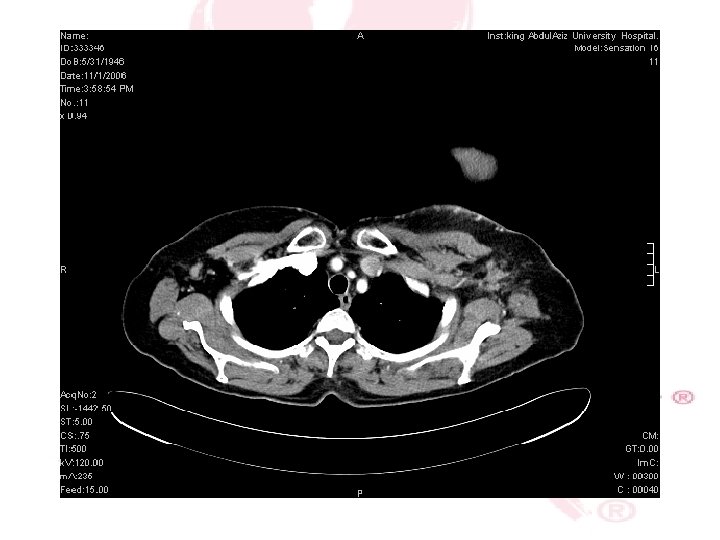

CHEST X-RAY